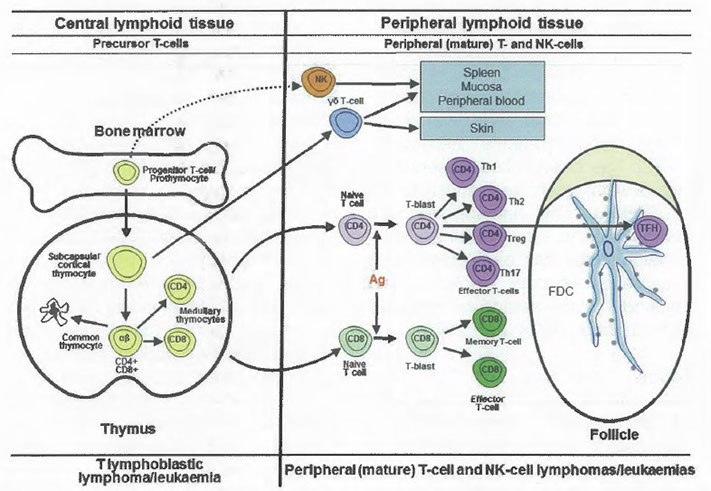

11 .01 The respective roles of various lymphocyte subpopulations in the immune system's two main arms: the innate and adaptive immune systems. In the innate immune system, which lacks specificity and memory, NK cells, NK-like T cells, and gamma delta T cells, along with other cells including granulocytes and macrophages, function as a first line of defence. These cells have cytotoxic granules (shown in red) containing perforin and granzymes. In the adaptive immune system, B cells and T cells recognize pathogens through specific receptors: immunoglobulins and the T-cell receptor complex, respectively. Antigen (Ag) presentation to T cells takes place via antigen-presenting cells (APCs) in the context of the appropriate major histocompatibility complex (MHC) class II molecule. Modified from Jaffe ES {1816}. [7]

11.04 T-cell differentiation. T cells mature in the thymus gland and then leave to occupy peripheral lymphoid tissues. T-cell receptor (TR) genes are shown schematically with a solid red bar indicating absence of rearrangement. The black boxes in the red bars reflect the rearrangements of the TR genes. The double red lines on the cell membrane represent the expressed T-cell receptor complex. Antigen dependent maturation leads to the different T-cell subsets, also illustrated in Fig. 11 .05. The phenotypes of several key T-cell subsets are illustrated:

T follicular helper (TFH), T regulatory (T-reg), T helper 1 (Th1), T helper 2 (Th2), and T helper 17 (Th17). Modified and updated from {3848). [7]

11.05 T-cell differentiation. T-cell neoplasms correspond to various stages of normal T-cell maturation. Mature T cells include alpha beta and gamma delta T cells, both of which mature in the thymus gland. Recently recognized T-cell subsets include the various types of CD4+ effector T cells, including T helper 1 (Th1), T helper 2 (Th2), T regulatory (Treg), T helper 17 (Th17), and T follicular helper (TFH) cells. Modified and updated from {3848). Ag, antigen; FDC, follicular dendritic cell. [7]